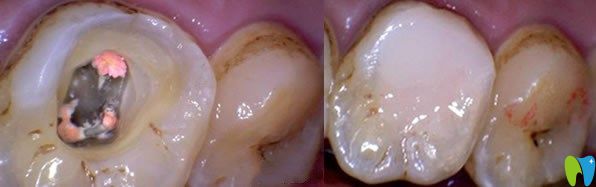

牙髓炎是一種嚴(yán)重的制病因素,一旦發(fā)炎不能好轉(zhuǎn),不是吃了消炎藥就可以恢復(fù),牙髓炎持續(xù)惡化,繼續(xù)發(fā)展就會(huì)造成牙髓死亡。牙齒沒有得到及時(shí)的診治,久而久之,牙齦就會(huì)萎縮,牙齒就會(huì)變得稀疏松動(dòng),導(dǎo)致牙齒脫落。

急性牙髓炎不治療的后果